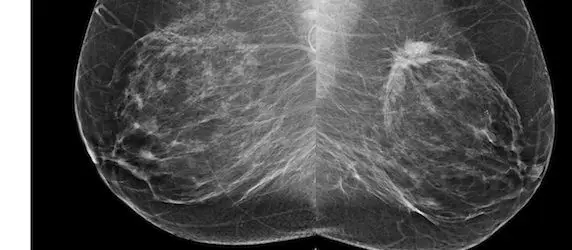

Figure 1 Patient 1: Bilateral mediolateral-oblique (MLO) views from screening mammography in a 53-year-old woman.

Figure 4 Bilateral MLO views.